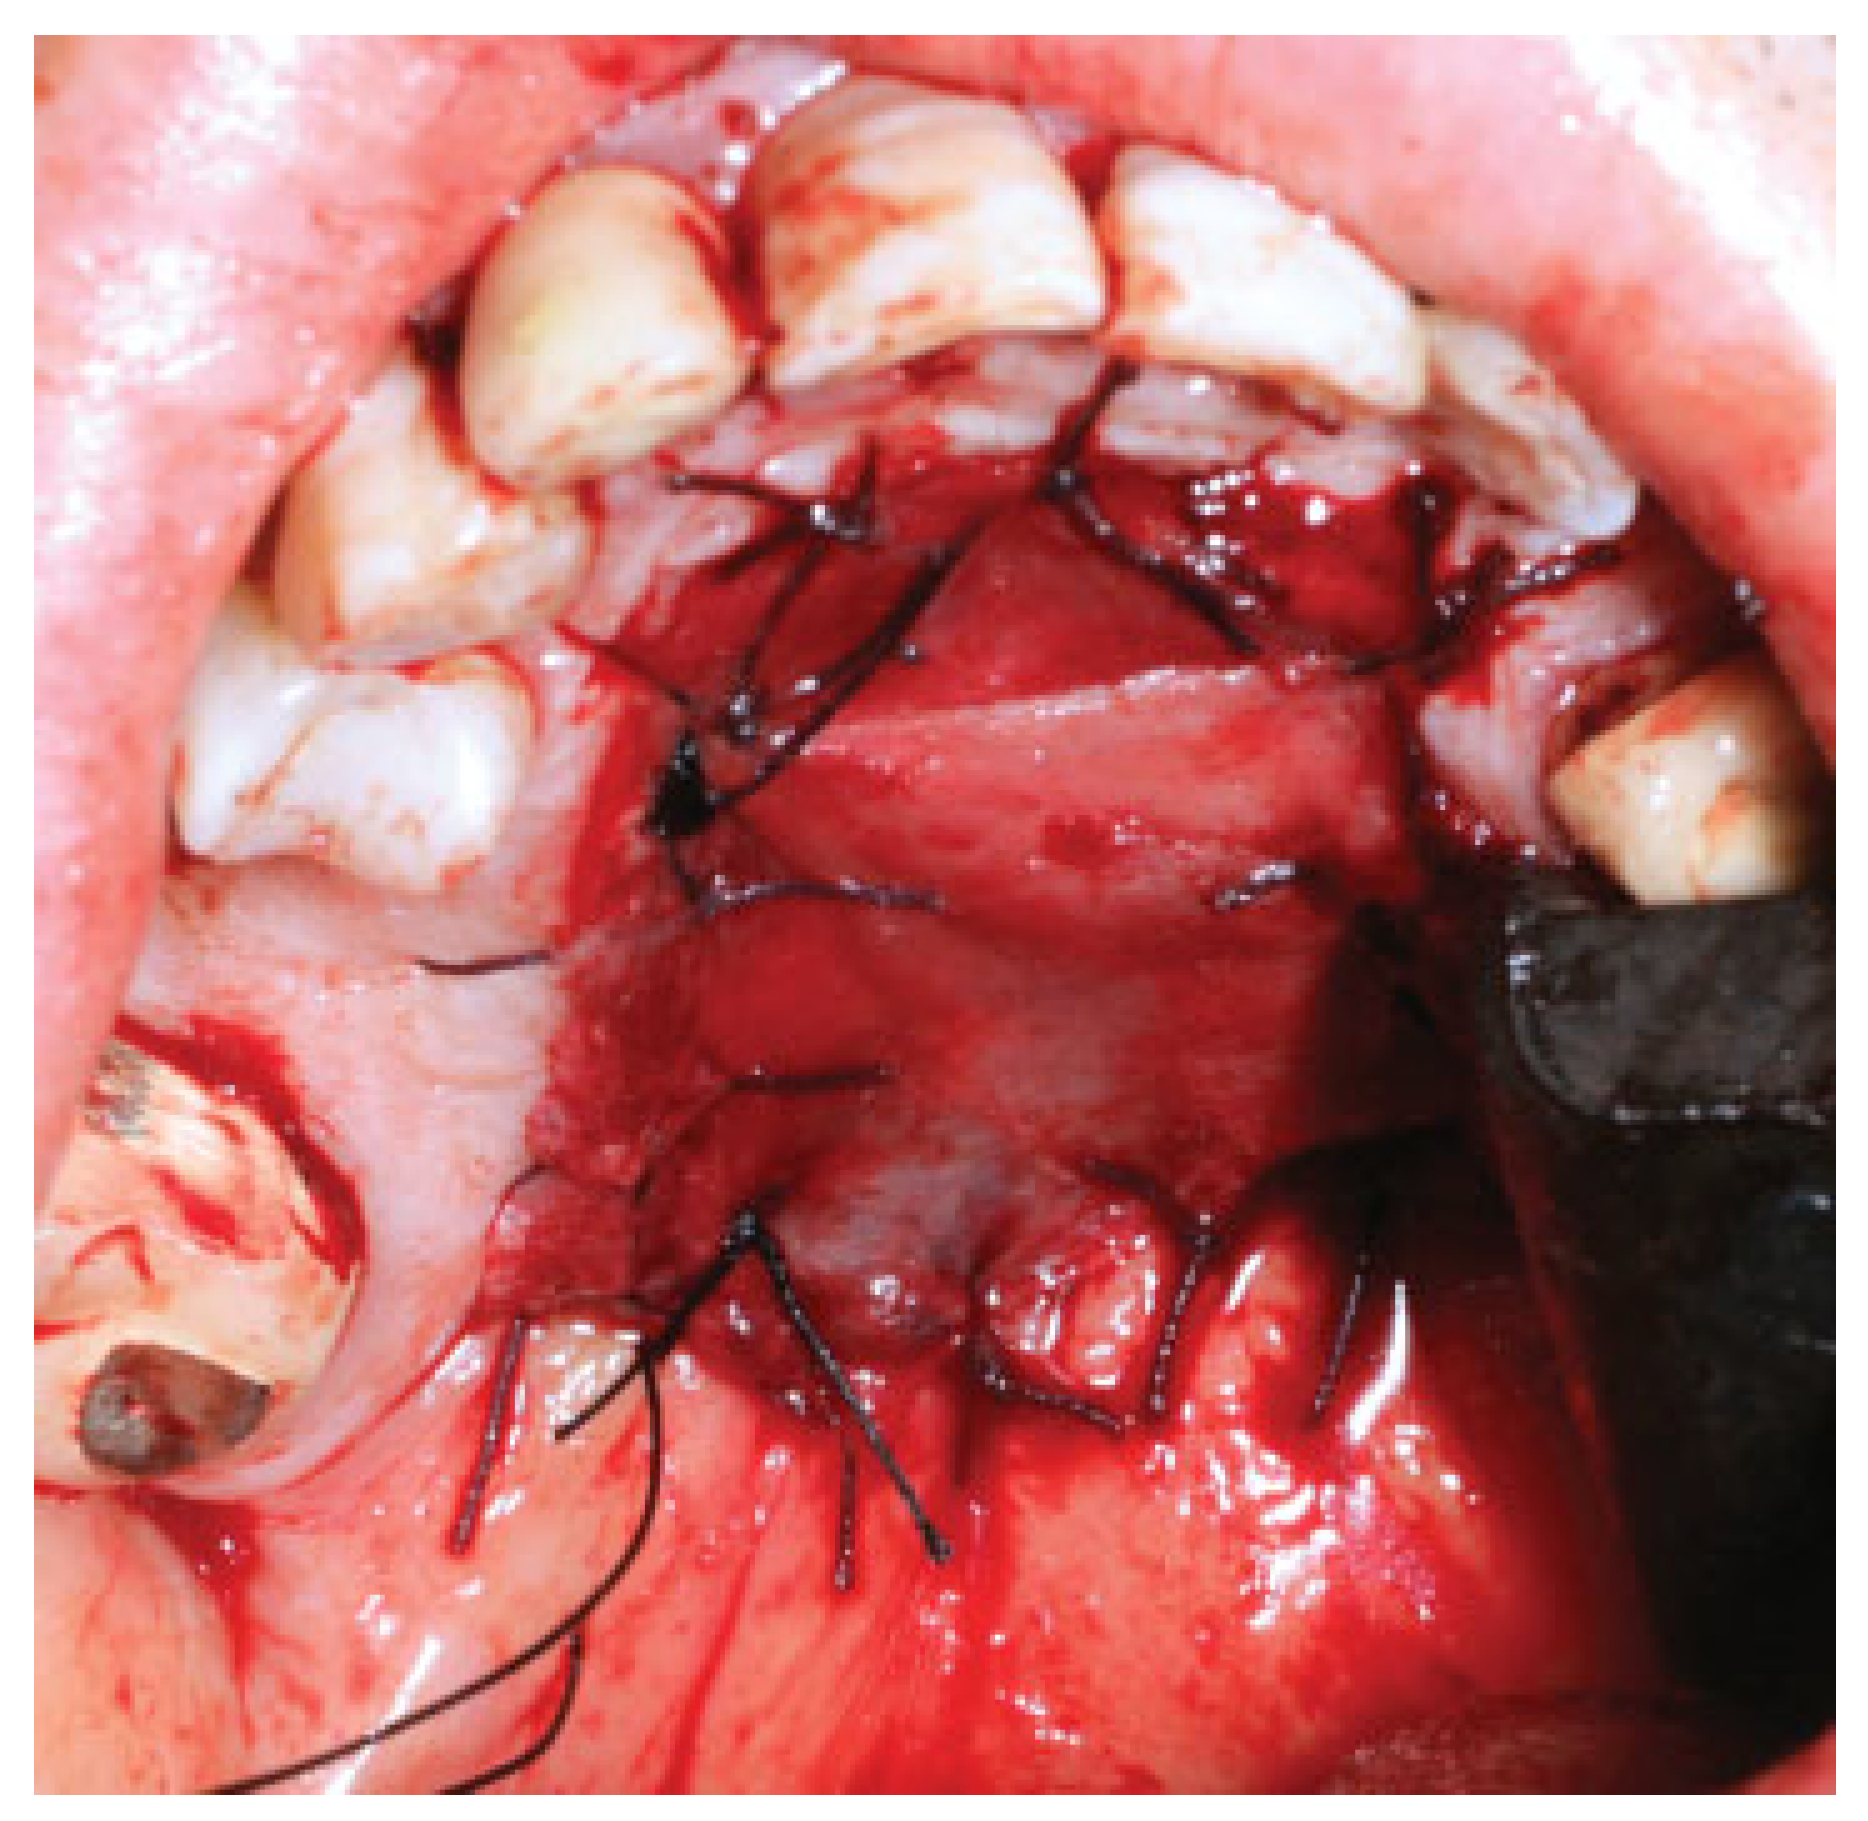

Once in the operating room, the kind of intubation should be individualized. For unilateral tumors, intranasal intubation is preferred to improve the intraoral visualization and facility tumor resection. Submental intubation represents an effective alternative especially with tumors affecting both nostrils. This technique places the endotracheal tube away from our surgical field and improves the tumor visualization. In the surgical technique, first, a free margin is delimitated on the palatine mucosa reaching the bone layer and a palatine osteotomy is done using an oscillating saw (Figure 1). Next, a vestibular maxillary approach is done and microplates are fixed at both sides of the maxilla to guarantee the correct reposition of the maxilla at the end of the procedure. Screws and microplates are removed and a Le Fort I osteotomy is performed. This represent the most critical point of the approach and attention must be directed to the piriform aperture, lateral nasal walls, and the septum in order to make the cuts without entering into the tumor. Preoperative imaging is crucial to determine the intranasal extension of the tumor and decide the level of the Le Fort osteotomy (Figure 2). Vertical extension of the tumor determines the most limiting factor and tumors with high intranasal extension may not be candidates for this kind of approach, as the risk of tumor disruption is higher in these cases.

Figure 1. Intraoperative detail of the tumor. A tumor-free margin is first designed on the palatine mucosa and bone.